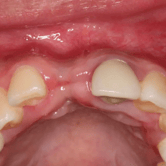

Pérdida de un diente único

La pérdida de un diente único es cuando un solo diente se ha caído o ha sido extraído, y se necesita un implante para reemplazarlo.

Los pacientes pueden notar un espacio donde solía estar el diente. Esta condición puede afectar la estética y la función masticatoria.

El tratamiento incluye la colocación de un implante dental para restaurar el diente perdido.